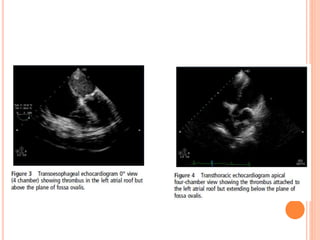

 IIa (attached to LA roof but above the plane of fossa ovalis)

 IIb (reaching below plane of fossa ovalis)

CLASSIFICATION  The thrombusin the left atrium can be classified as (Manjunath et al.) -  Ia (thrombus confined to LAA)  Ib (thrombus in LAA and protruding into LA cavity)  IIa (attached to LA roof but above the plane of fossa ovalis)  IIb (reaching below plane of fossa ovalis)  III (attached to interatrial septum)  IV (mobile with attachment to roof or lateral wall)  V (ball valve thrombus)